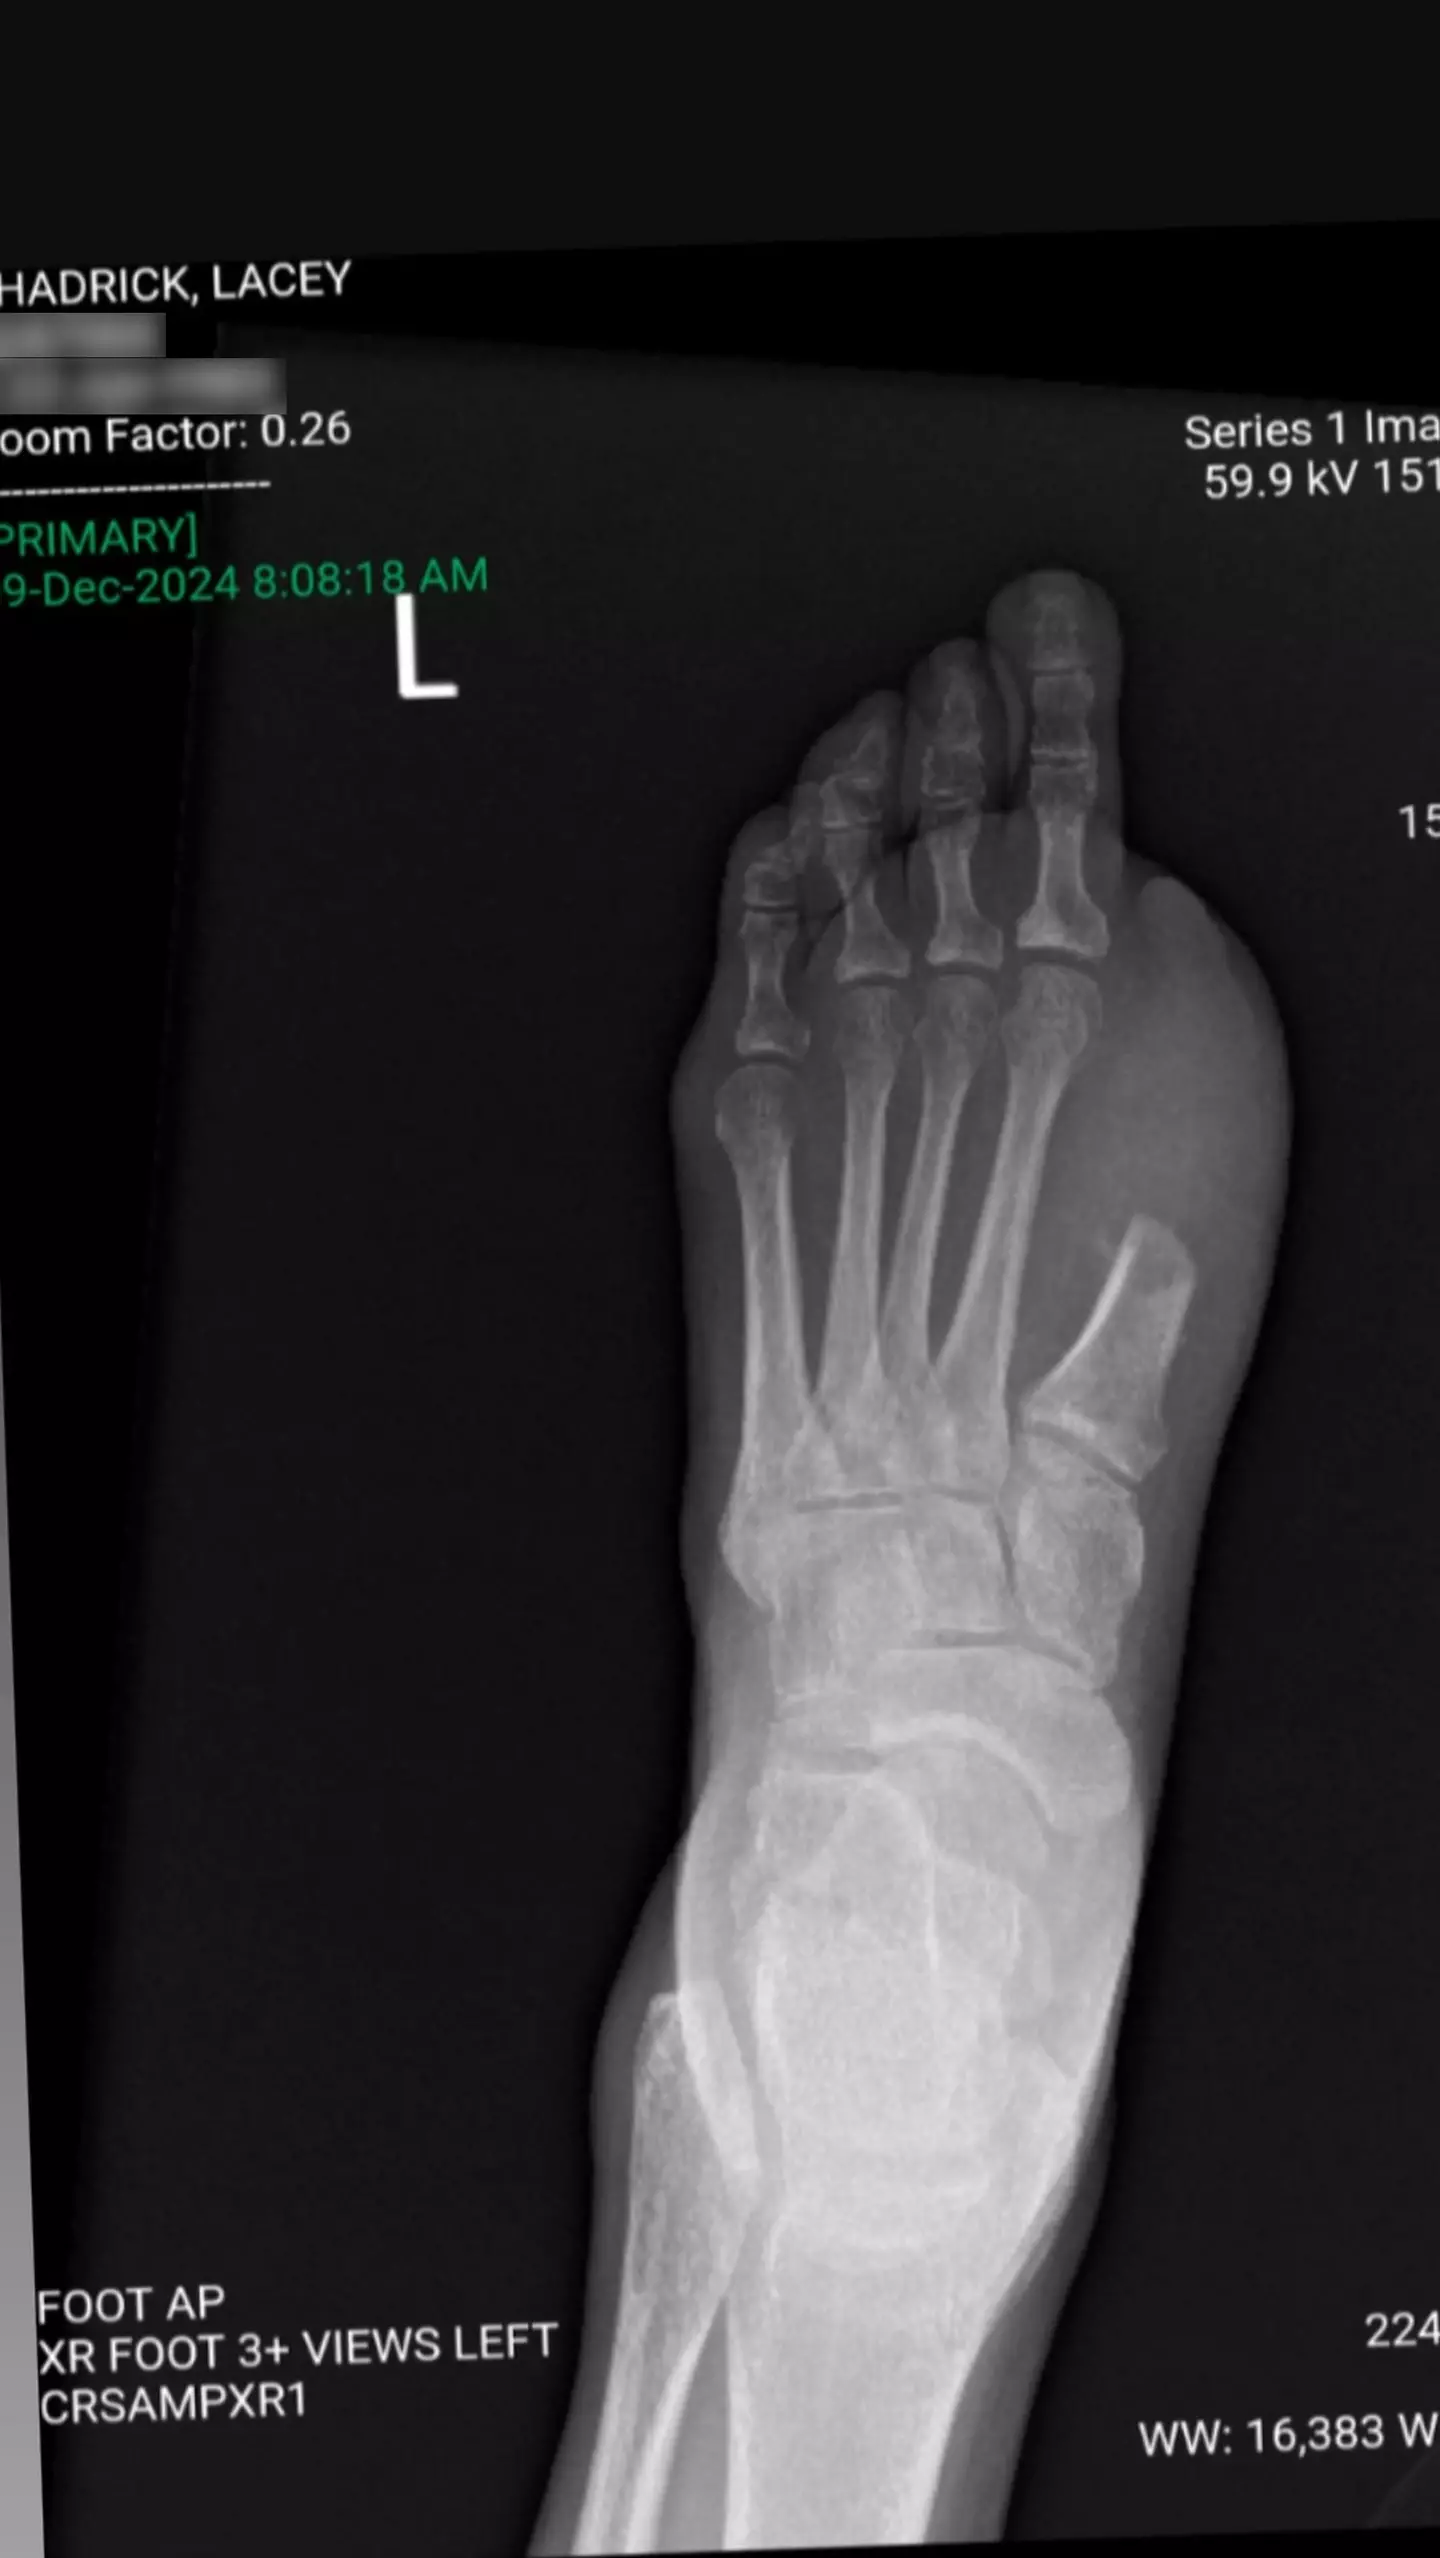

Scans revealed her 'foot was a mangled mess on the inside', and she's now encouraging people to 'trust your body' if they think something is wrong.